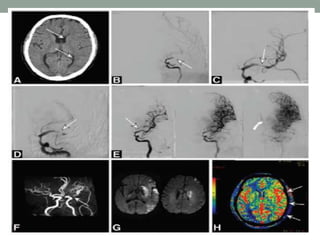

Intra-arterial Fibrinolysis

PROACT II –

• To test the effectiveness of intra-arterial fibrinolysis using r-

pro-UK to treat MCA (M1 or M2) occlusions within 6 hours of

stroke symptom onset.

• 40% of the 121 patients treated with r-pro-UK and 25% of the

59 control patients had an mRS score of 0 to 2 at 90 days

(P=0.04). MCA recanalization was achieved in 66% of the r-

pro-UK arm and 18% of the control group (P=0.001). sICH

occurred in 10% of patients treated with r-pro-UK and in 2% of

the control group (P=0.06).

• Use of intra-arterial fibrinolysis for occlusions in additional

locations, such as the basilar artery and intracranial carotid

artery, is based primarily on consensus and case series.

• Meta-analysis of multiple case series comparing intravenous

with intra-arterial fibrinolysis for acute vertebrobasilar stroke in

422 patients showed marginally better recanalization rates with

intra-arterial therapy (65% versus 53%; P=0.5), good

neurological outcomes in 22% to 24% of patients, but no clear

difference in efficacy between the 2 modalities

• Results of PROACT-II were considered insufficient to grant

FDA approval

• Intra-arterial fibrinolysis is a consideration for patients

ineligible for intravenous rtPA

a. Treatment within 4.5 to 6 hours;

b. Recent history of a major surgical procedure